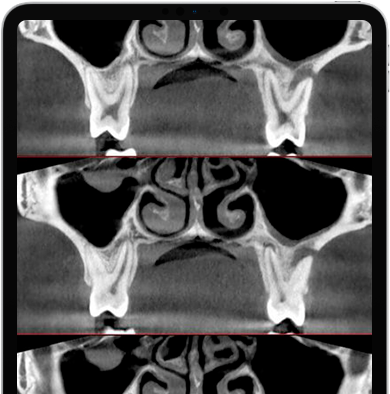

GO 2D / 3D possui um único sensor nativo de 16 bits que produz imagens 2D e 3D com milhares de níveis de cinza. A qualidade da imagem é garantida por algoritmos e protocolos avançados e por sequenciamento de imagens de alta tecnologia. O gerador de emissão pulsada de alta frequência ajusta a exposição para obter as melhores varreduras com uma dose mínima.

NewTom GO gera excelentes imagens volumétricas e para cada FOV, variando de 6 x 6 a 10 x 10 cm. A escolha de 3 protocolos permite que a dose de raios-X necessária seja adaptada às necessidades específicas: desde muito baixa para varreduras rápidas exigidas por verificações de acompanhamento cirúrgico, passando por planejamento regular de tratamento, até um nível muito alto de detalhes para a análise de microestruturas.

Imagem de alta qualidade com uma dose de radiação muito baixa. Protocolos definidos pela pesquisa da NewTom em mais de 20 anos de experiência permitem adaptar automaticamente a exposição com base nas características anatômicas do paciente, no distrito anatômico examinado e nas reais necessidades diagnósticas.